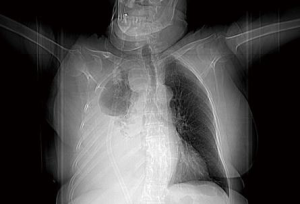

A chest radiograph at six weeks showed bilaterally well expanded lungs (Figure 5).

Figure 5 Post-operative chest X-ray at 6 weeks. The right lung is fully expanded and the paratracheal mass has been fully excised.

Follow up at eight weeks revealed normal calcium and PTH levels.